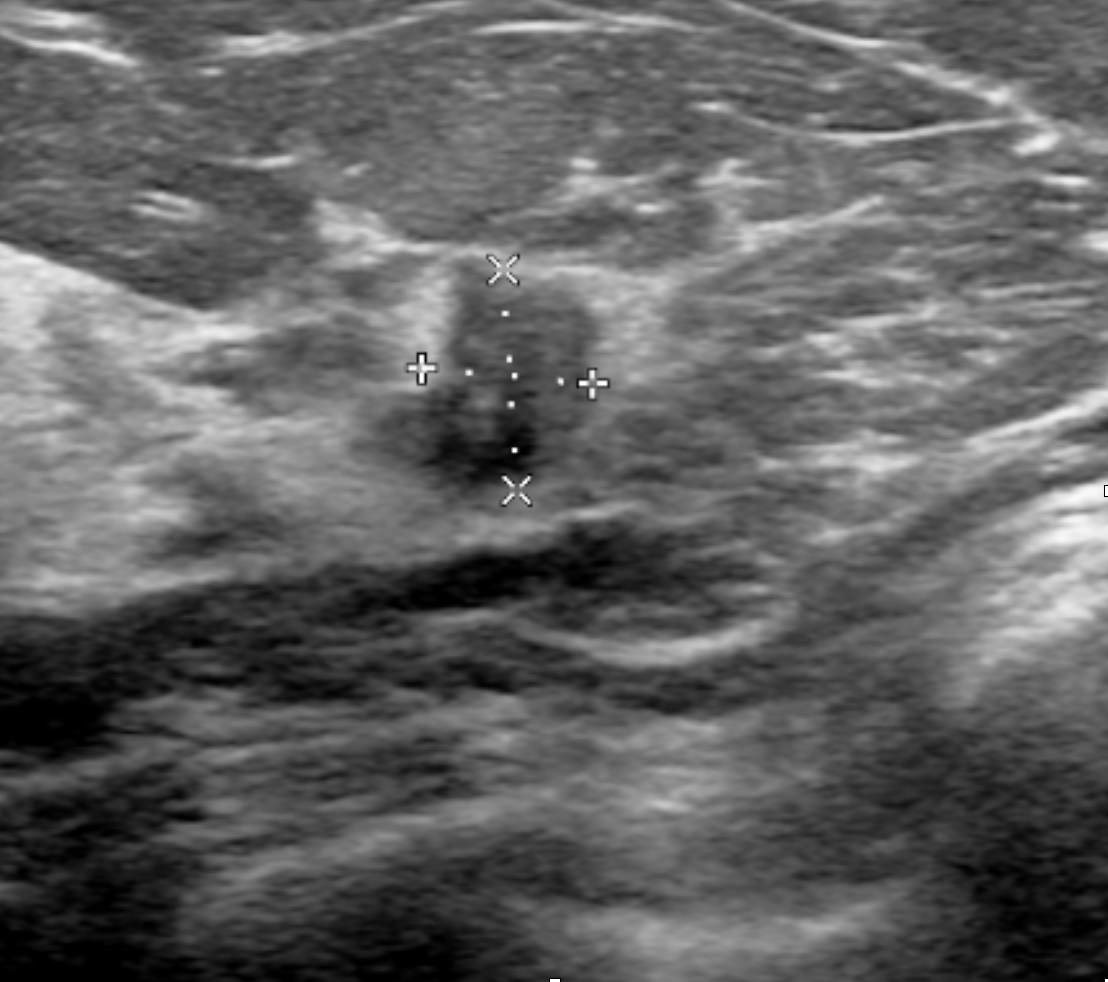

In Figure 7, we visualize saliency maps for four samples selected from the test set. In the first two examples, the saliency maps are highly activated on the annotated lesions, suggesting that our model is able to detect suspicious lesions without pixel-level supervision. Moreover, the attention is highly concentrated on ROI patches that overlap with the annotated lesions. In the third example, the saliency map for benign findings identifies three abnormalities. Although only the top abnormality was escalated for biopsy and hence annotated by radiologists, the radiologist’s report confirms that the two non-biopsied findings have a high probability of benignity and a low probability of malignancy. In the fourth example, we illustrate a case when there is some level of disagreement between our model and the annotation in the dataset. The malignancy saliency map only highlights part of a large malignant lesion with segmental coarse heterogeneous calcifications. This behavior is related to the design of : a fixed pooling threshold cannot be optimal for all sizes of ROI. The impact of is further studied in 3.6. This example also illustrates that while human experts are asked to annotate the entire lesion, CNNs tend to emphasize only the most informative regions. While no benign lesion is present, the benign saliency map still highlights regions similar to that in the malignancy saliency map, but with a lower probability than the malignancy saliency map. In fact, calcifications with this morphology and distribution can also result from benign pathophysiology [42].

In addition, we observe that GMIC is able to provide meaningful localization when the lesions are hardly visible to radiologists in the image. In Figure 8, we illustrate a mammographically occult mammogram of a 59-year old patient with no family history of breast cancer and dense breasts. There is an asymmetry in the left lateral breast posterior depth which appears stable compared to prior mammograms and was determined to be benign by the reading radiologist. However, the saliency map of malignant findings successfully identifies the malignant lesion on the screening mammogram. Same day screening ultrasound (sagittal image) demonstrated a 1.2 cm irregular mass; ultrasound biopsy yielded moderate grade invasive ductal carcinoma.